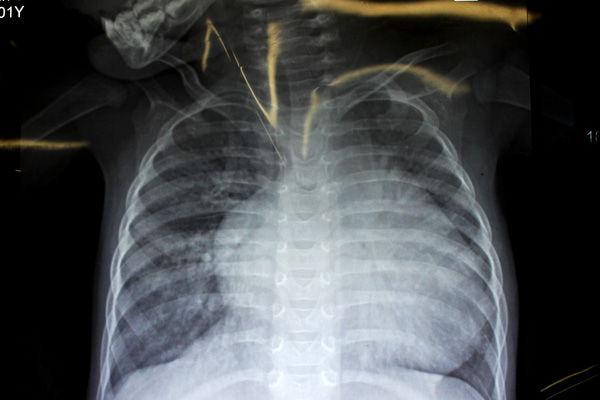

“别以为她的人小,心脏就跟着小,因为患了严重的心脏病,小鑫怡心脏却大得像个大大的皮球!”在心胸外科医生办公室,杨柳山副主任医师向笔者展示了小鑫怡的X光胸片,只见小小的胸腔里,一团白色心脏阴影几乎占满了半个胸部的视野,那是小鑫怡的心脏,就是这颗发育异常的心脏,让小鑫怡降临到这世上的10个多月里,吃尽了苦头。

小鑫怡术前的X光胸片,可以看到心脏大得像个球